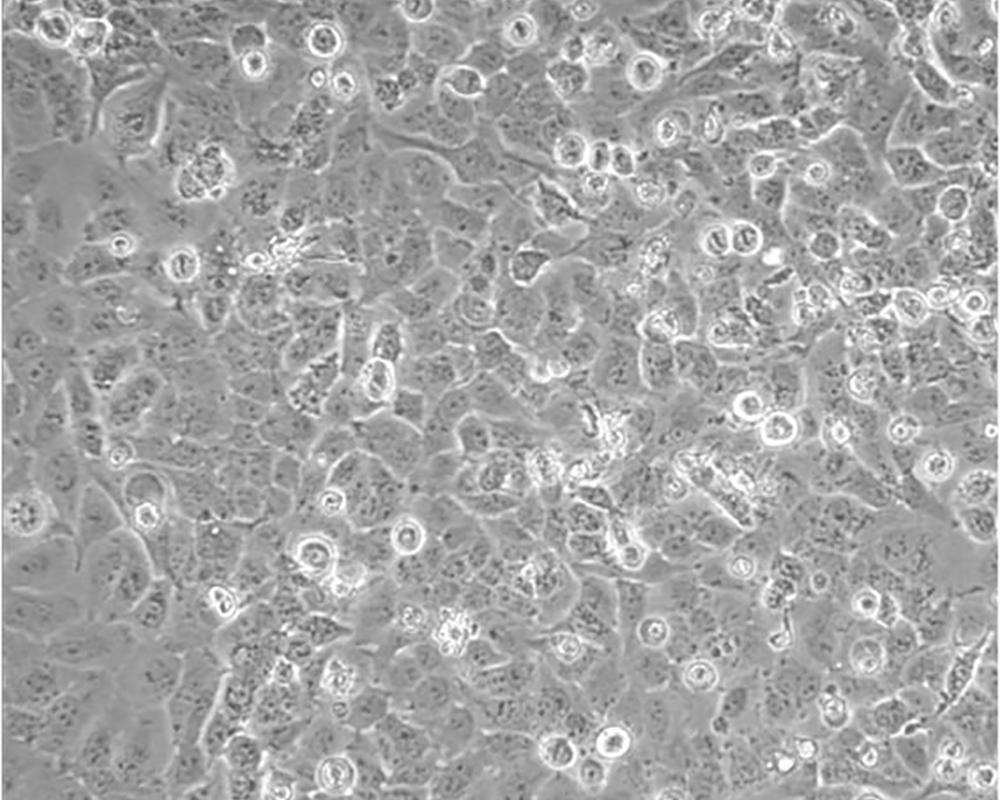

NCI-H23

產(chǎn)品名稱 NCI-H23

組織來源 肺腺癌;男性

細胞種屬 Homo sapiens, human

生長特性 Homo sapiens, human

培養(yǎng)基 RPMI-1640+10% FBS+1% P/S

形態(tài)特征 epithelial

傳代方法 1:3-1:6

培養(yǎng)條件 Atmosphere: Air, 95%; CO2, 5%。Temperature: 37℃

細胞描述 該細胞源于一位51歲患有非小細胞肺癌黑人男性患者的治療前的腫瘤組織,表達C-myc、L-myc、v-src、v-abl、v-erb B、c-raf 1、Ha-ras、Ki-ras、N-ras RNAs;該細胞攜帶K-ras 12突變;p53基因246位密碼子突變ATC→ATG;表達PDGF A和B鏈的異源mRNA;表達TGFα、TGFβ和EGFR;角蛋白 5、8和18陽性,波形蛋白陽性,神經(jīng)絲蛋白陰性,左旋多巴脫氫酶陰性;據(jù)報道,在軟瓊脂中該細胞形成克隆的效率為9.7%。